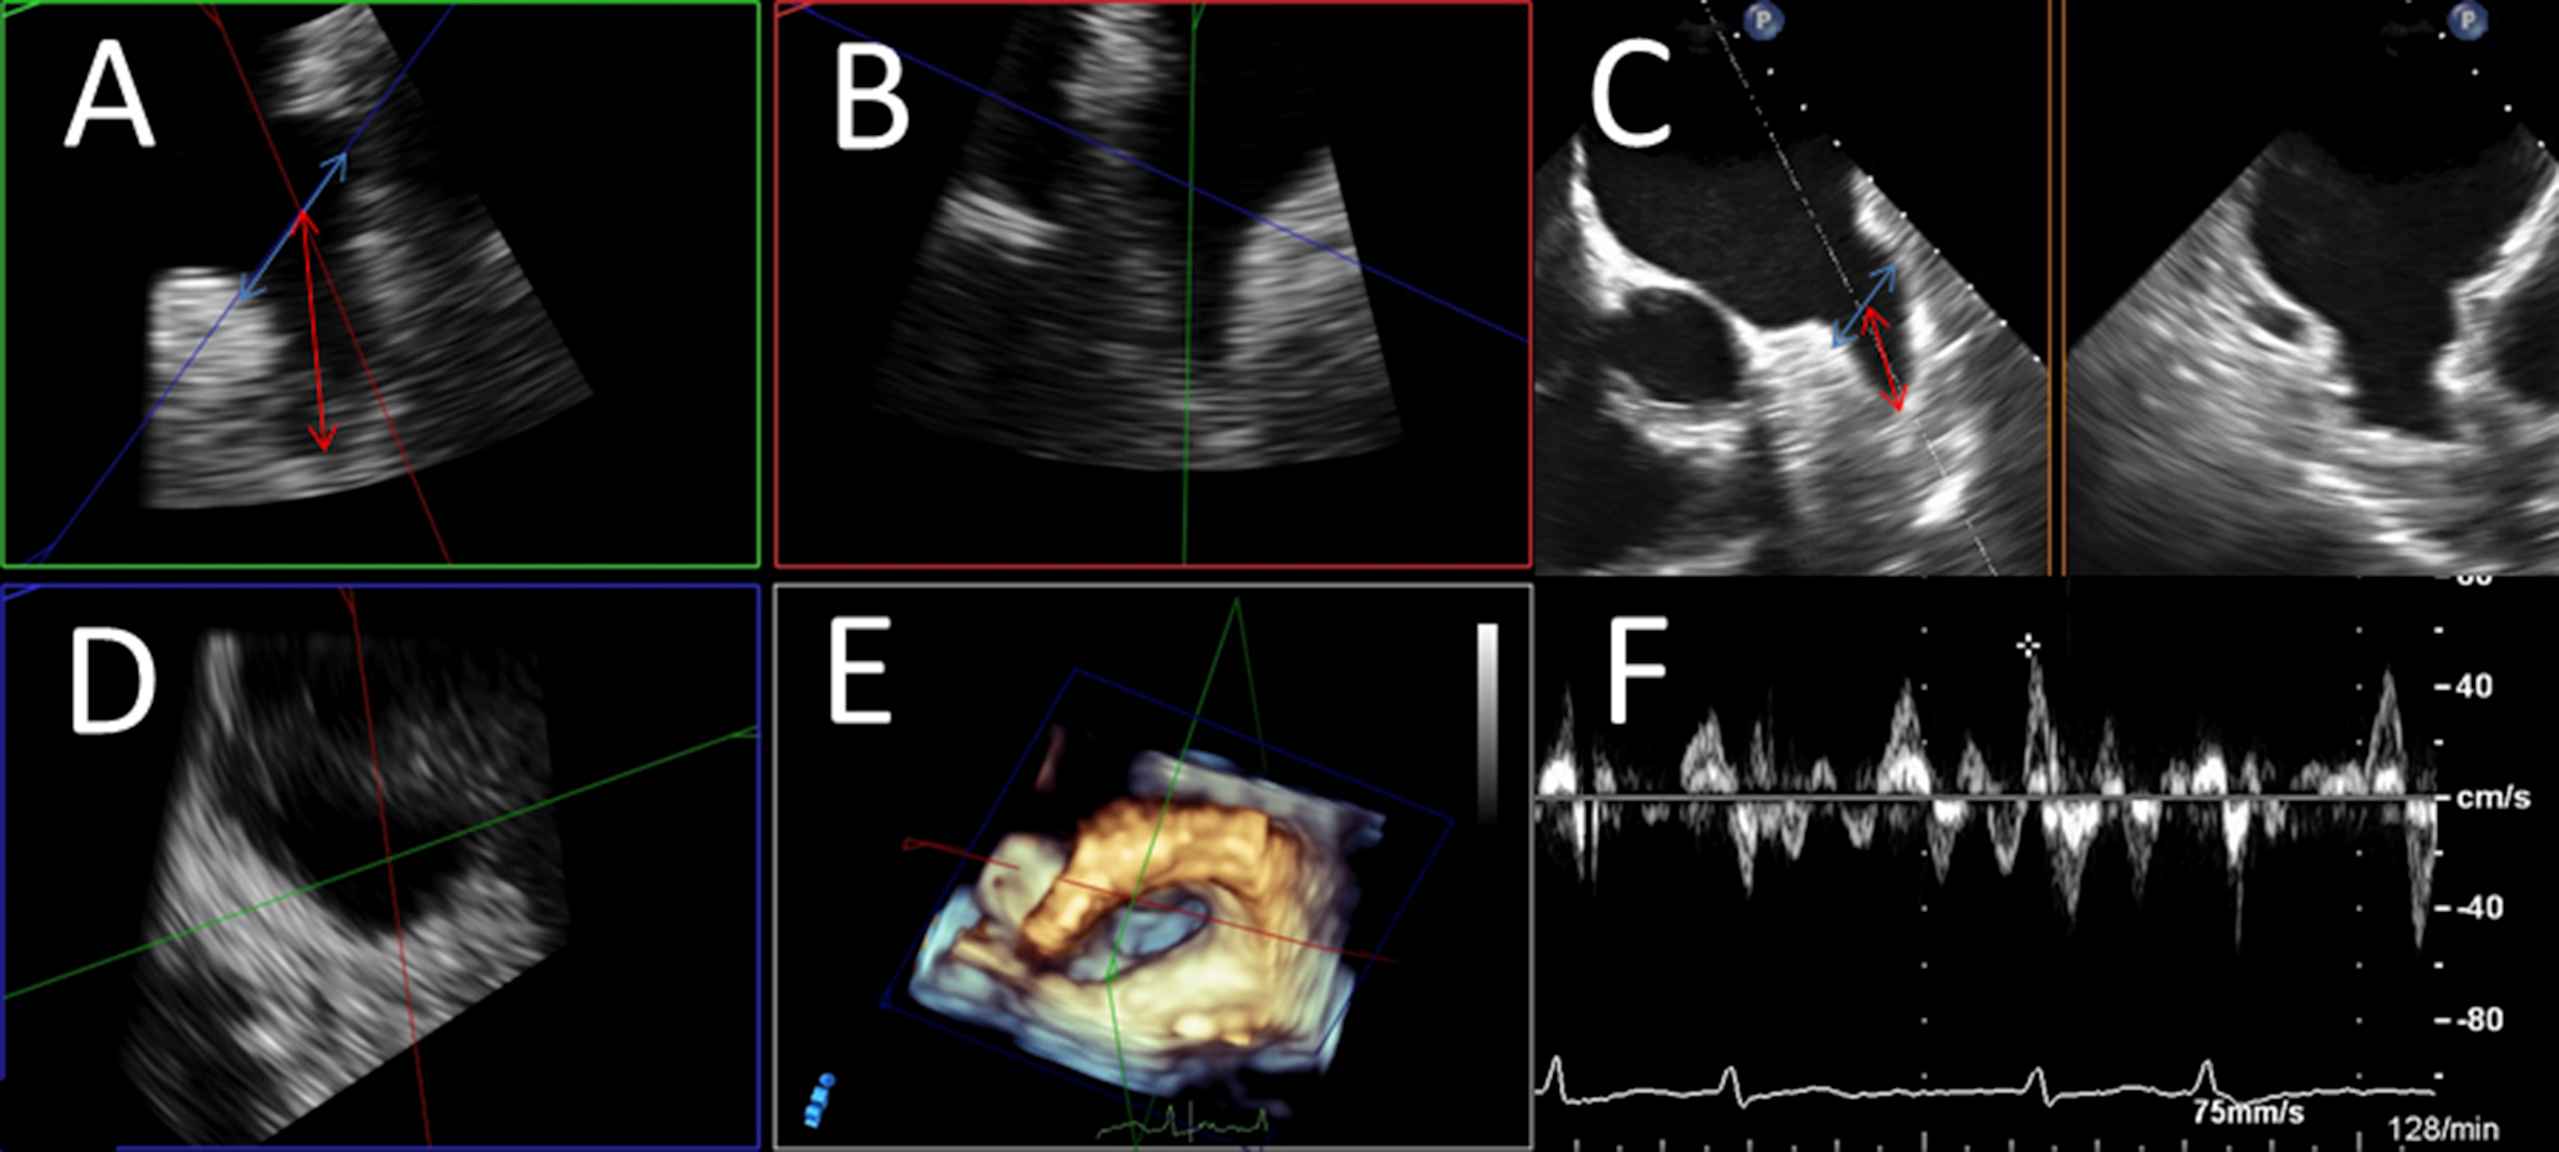

We assessed patients’ anthropometric and clinical characteristics, comorbidities and echocardiographic parameters. The CHA2DS2-VASc-score (Congestive heart failure, Arterial Hypertension, Age ≥75 years, Diabetes mellitus, prior ischemic Stroke, TIA or thromboembolism, Vascular disease, Age 65–74 years, female sex (but female sex is only a risk factor if other risk factors are also present))33 was calculated for all patients. Echocardiographic measurements were obtained by evaluation of two- and three-dimensional TTE and TEE loops stored on the clinic’s server in DICOM-standard and assessment via Philips Xcelera® and Qlab® software (trademark by Philips® healthcare). All echocardiographic analyses were performed and confirmed by at least two experienced echocardiographers. The echocardiographic measurements comprised evaluation of thrombogenic material, which was defined as the presence of solid thrombi or relevant spontaneous echo contrast (SEC) in the LAA, blood flow velocity in LAA detected by Pulsed-waved (PW)Doppler as well as the spatial dimensions of the LAA in kind of width (septal-lateral diameter obtained in short axis view/45° angulation) and length (aperture-apex) of the LAA in TEE (Fig. 1). Confirmation or exclusion of atrial thrombi or SEC was performed in all recorded angulations and three-dimensional reconstructions, if available.

Assessment of LAA diameters and LAA velocity. LAA expansions were measured by determining orifice width and LAA depth. LAA orifice width (marked as red arrow) was estimated by measuring septo-lateral diameter in short axis view (SAX) as an approximated plane from the left coronary height (septal) to 1–2 cm below the highest point of the LUPV (left upper pulmonary vein)-limbus (“rim”/lateral); LAA depth (marked as blue arrow) was determined as distance from orifice plane to the deepest point of the LAA. If available, measurements were performed by multi-planar reconstruction of three-dimensional echo loops (Panels A, B, D: Panel A shows a reconstructed plane resembling SAX-view in left upper quadrant, Panel B another reconstructed longitudinal plane orthogonal on Panel A, Panel D the reconstructed “orifice” of the LAA). Panel C demonstrates measurements in “conventional” 2-dimensional TEE at about 45° resembling SAX-view. Panel E shows spatial relations in the LA in a three-dimensional overview in “non-surgical” orientation. Panel F shows the determination of blood velocity in the LAA via PW-doppler in a patient with present atrial fibrillation (obviously shown by PW-curve demonstrating rapid and irregular LAA contractions).

Left ventricle ejection fraction (LVEF), left and right septal-lateral and longitudinal diameters as well as atrial areas and systolic pulmonary artery pressure were measured, if a TTE was available (from the same hospital visit). Ventricular dimensions, LVEF and atrial areas were determined in apical 4 chamber view using Simpson’s method according to the EACVI- and ASE-recommendations on cardiac chamber quantification.34 Proposed systolic artery pressure (sPAP) was estimated from Doppler regurgitation velocity on tricuspid regurgitation (Fig. 1).